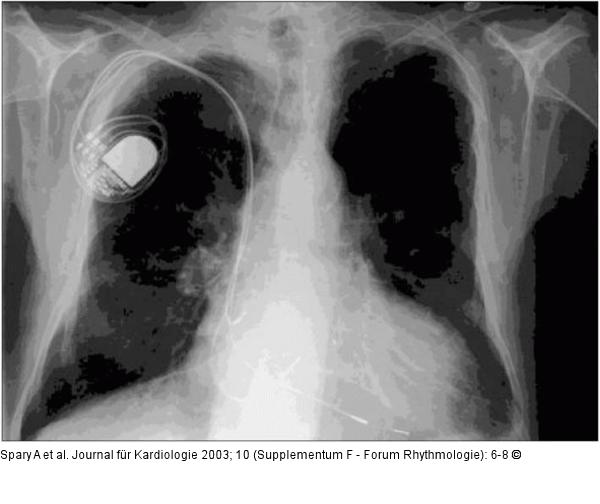

Abbildung 2: Biventrikulärer Herzschrittmacher Biventrikulärer Schrittmacher im Thorax-Röntgen; auffällig ist, daß neben einer normalen Stimulationselektrode im rechten Vorhof und im rechten Ventrikel eine dritte Sonde über den Sinus coronarius an den linken Ventrikel herangeführt wird. |

Abbildung 2: Biventrikulärer Herzschrittmacher

Biventrikulärer Schrittmacher im Thorax-Röntgen; auffällig ist, daß neben einer normalen Stimulationselektrode im rechten Vorhof und im rechten Ventrikel eine dritte Sonde über den Sinus coronarius an den linken Ventrikel herangeführt wird. |